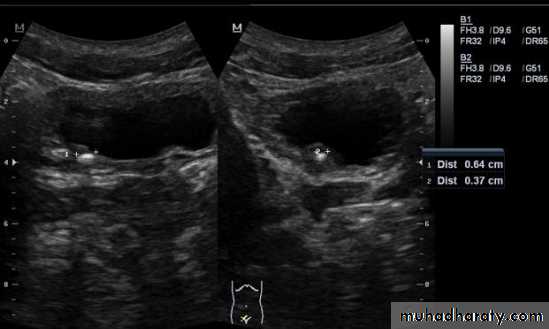

2-Stones larger than 5 mm are easily seen on US but smaller ones may be missed.

-They produce intense echoes (hyperechoic) and cast acoustic shadows.

-Proximal and distal ureteric dilatation can be easily identified unlike mid-ureteric dilatation, and stones located in the middle third of the ureter are hard to be demonstrated unlike upper and lower ureteric stones (especially those lodged in the vesico-ureteric junction or pelvi -ureteric junction) which are easily identified by ultrasound.